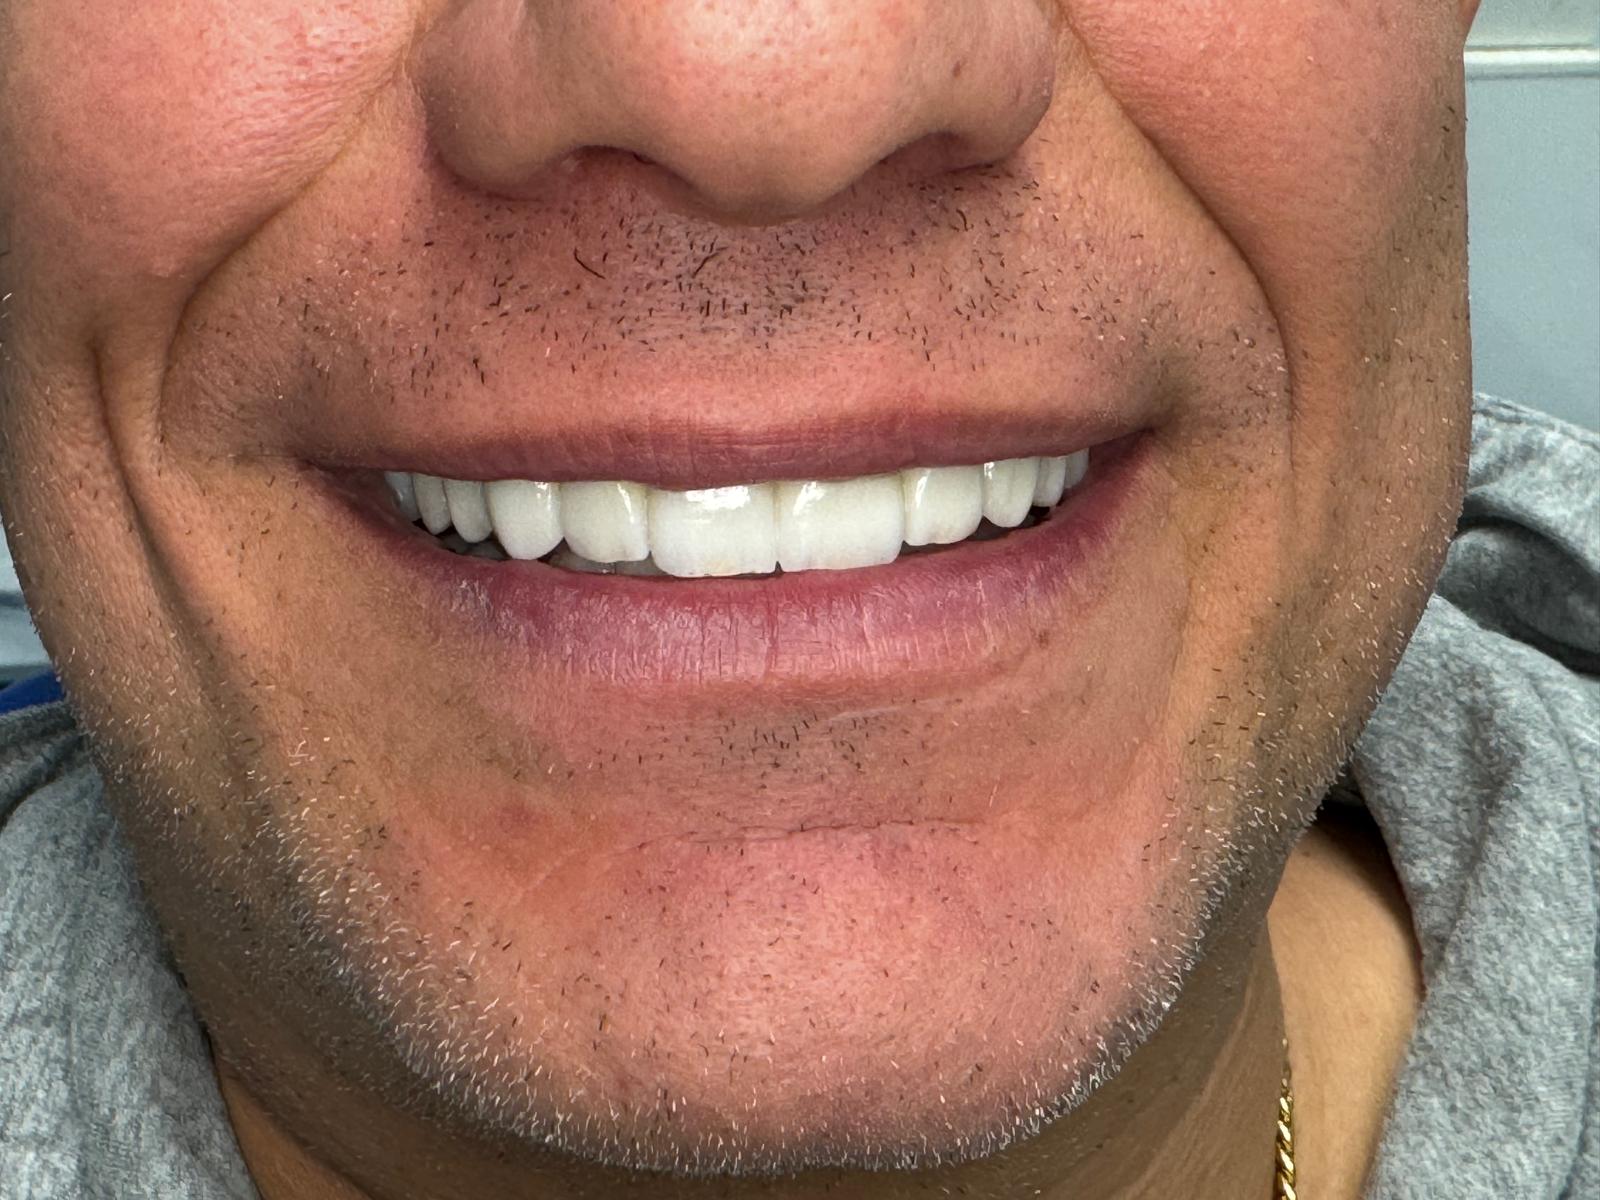

Volver a sonreír sin pensarlo.

No es magia. Es planificación digital, coronas de cerámica de primera calidad y el Método Gnadent. El paciente de estas fotos recuperó su sonrisa — y la libertad de mostrarla.

Casos Antes y Después

Pacientes reales, resultados reales. Desliza para explorar.

← Arrastra para explorar →